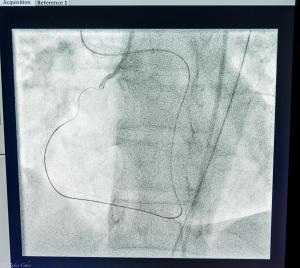

CTO Case 2017 Carmel Hospital Israel